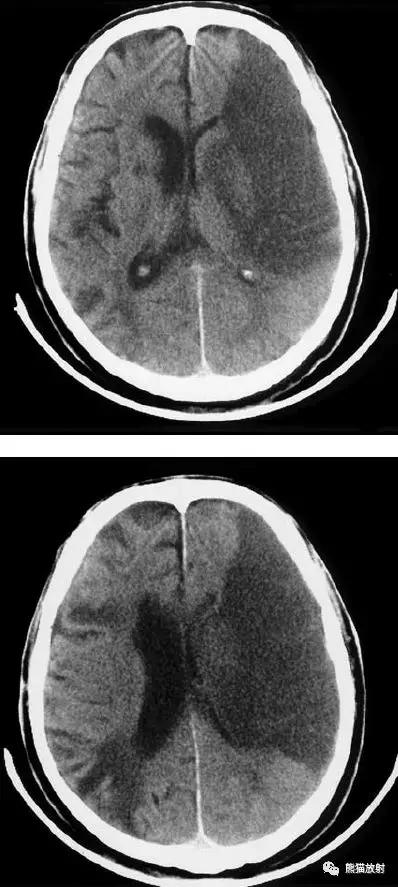

右侧大脑前、中动脉供血区梗死,可见明显占位效应。

右侧大脑前、中、后动脉供血区巨大梗死

分水岭脑梗死(“Watershed” infarcts):右侧大脑前中动脉及中后动脉供血区之间梗死灶。

分水岭脑梗死:左侧深部和浅部大脑中动脉供血区之间梗死灶。

左侧尾状核头脑梗死;右侧外囊腔隙性脑梗死。